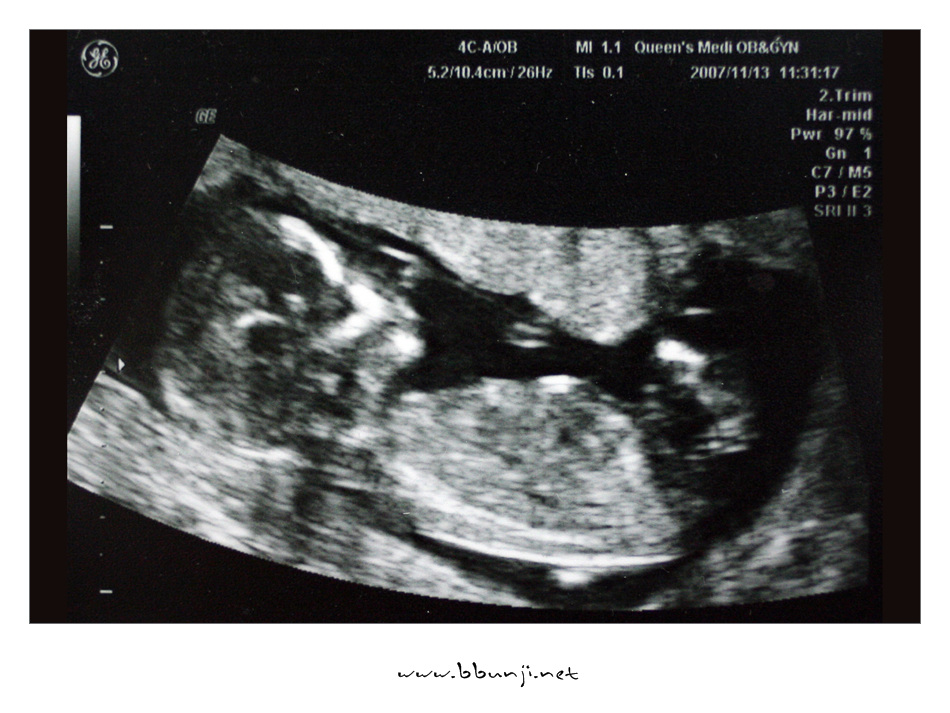

사랑이… 14주 째.. *^^*

2007년 11월 13일

이제 우리 사랑이 제법 키가 커서 8cm가 다 되었습니다.

배초음파를 하는데 첨에는 손깍지 끼고 다리 오므리고 있다가 팔도 움직이고 다리도 움직이더라구요.

이제 척추랑 갈비뼈도 완전히 보이고 손모양도 얼추 제법 모습이 보이네요.

의사 선생님이 코가 오똑하답니다.ㅋㅋㅋ

그 작은 것이 꼬물거리고 심장이 뛰는거 보니 희안하다 못해 신비하기까지 합니다.